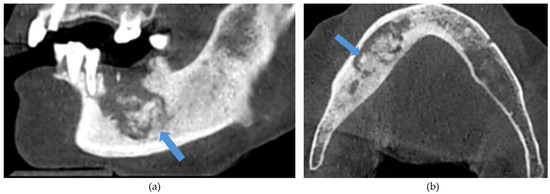

Figure 3. (a) Sagittal and (b) axial sections and (c) 3D reconstructed image demonstrating a left angle of the mandible pathological fracture resulting from stage III MRONJ.